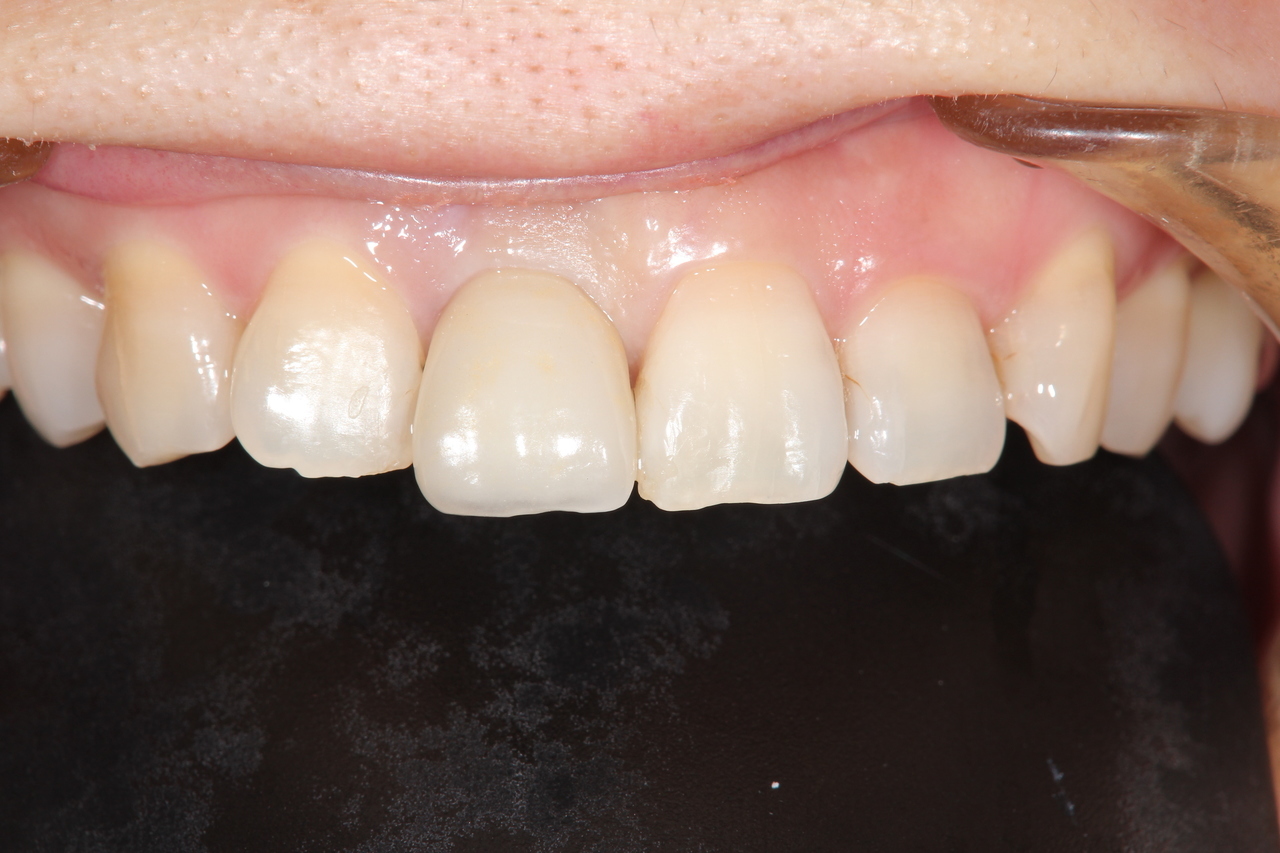

前歯インプラント(美しさを重視した場合は、ジルコニアでセメント固定がお勧めです。前歯の場合は、歯肉の形をシャープできれいな形にする為、仮歯が必要です。)

(下田市在住 女性)

治療の流れ

前歯破折

神経を取って差し歯にしていた歯根が破折したため、抜歯することになりました。

前歯インプラント土台

前歯部の審美領域は、白い土台など、より綺麗に見せるオプション費用が追加になります。

前歯インプラント

最終的な被せ物を装着すると、隣の天然歯と見分けがつかない綺麗な仕上がりになりました。

インプラント手術:250,000円

静脈内鎮静法:0円

仮歯:50.000円

ジルコニアアバットメント:120,000円

前歯用プレミアムジルコニア:150,000円

総額:570,000円+税